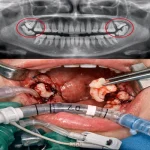

تزریق بیحسی در لثه کنار دندانهای شدیداً پوسیده

جراحیهای دندان و دهان؛ شامل جراحی دندان نهفته و جراحیهای تهاجمی

ایمپلنت دندان؛ بهعلت سوراخکاری استخوان و کاشت پایه ایمپلنت

جراحی لثه؛ بهدلیل برش و دستکاری بافت نرم

پیوند استخوان فک؛ با درگیری مستقیم استخوان و بافت اطراف

سینوس لیفت؛ بهعلت مداخله در ناحیه سینوس و استخوان فک بالا